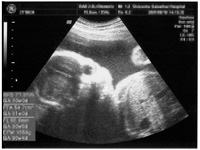

病院の診察で頂くエコー(echo・超音波検査)は感熱紙(FAXなどと同じ原理)が多く、保存の状況によってはエコーが見えなくなる可能性があります

3Dや4Dのエコーはインクジェットの可能性があります |